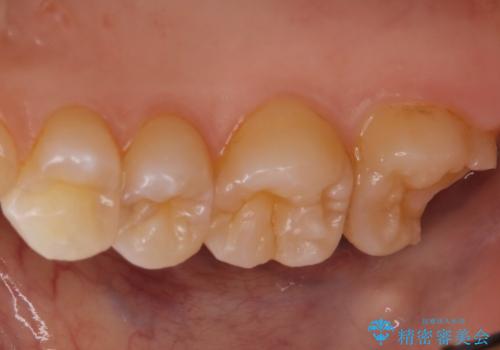

- 他院にて虫歯を指摘され、セカンドオピニオンを希望し当院へ来院されました。以前より磨きずらさと舌感の悪さは自覚していたそうです。清掃性、機能性に優れたセラミックインレーにて治療をすることとなりました。

レントゲンから昔詰めた保険の詰め物が入っていることが確認できました。詰め物と歯の隙間が虫歯になっていたためしっかり取り除き、適合の良いセラミックインレーを入れました。